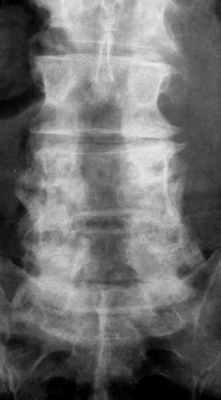

Лучевая диагностика синдрома оперированного позвоночника

![стеноз в пояснице в цвете]()

МРТ поясничного отдела позвоночника. Т2-взвешенная сагиттальная МРТ. Стеноз позвоночного канала.

Оценка состояния поясничного отдела позвоночника после операции составляет важную и сложную задачу. МРТ СПб позволяет выбирать место обследования после операции. От правильной трактовки выявленных изменений зависит выбор дальнейшей тактики лечения пациента. Современный взгляд на проблему может быть назван «междисциплинарным», так как требует кооперации специалистов разного профиля: спинальных хирургов (нейрохирургов), лучевых диагностов, специалистов-реабилитологов (физиотерапевтов и т.д.).